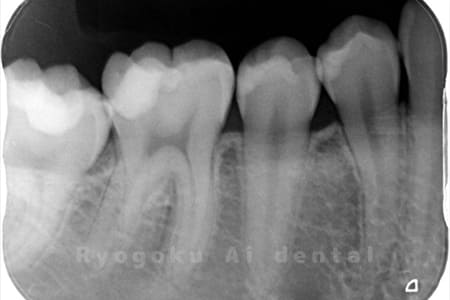

Case02

-

- 原因

- C3、インレー不適合

- 治療期間

- 1ヶ月

- 治療内容

- 断髄治療

- 治療費用

- 66,000円

虫歯の治療と銀歯のやり直しを希望され、銀歯を外したところ、虫歯が大きく、神経の処置が必要と判断。患者様と相談し、神経を残す断髄治療となったケース。

<リスク・副作用>

術後は痛み、腫れ、痺れなどの副作用が生じる場合があります。症状が再発する可能性があります。その場合は抜髄する必要があります。